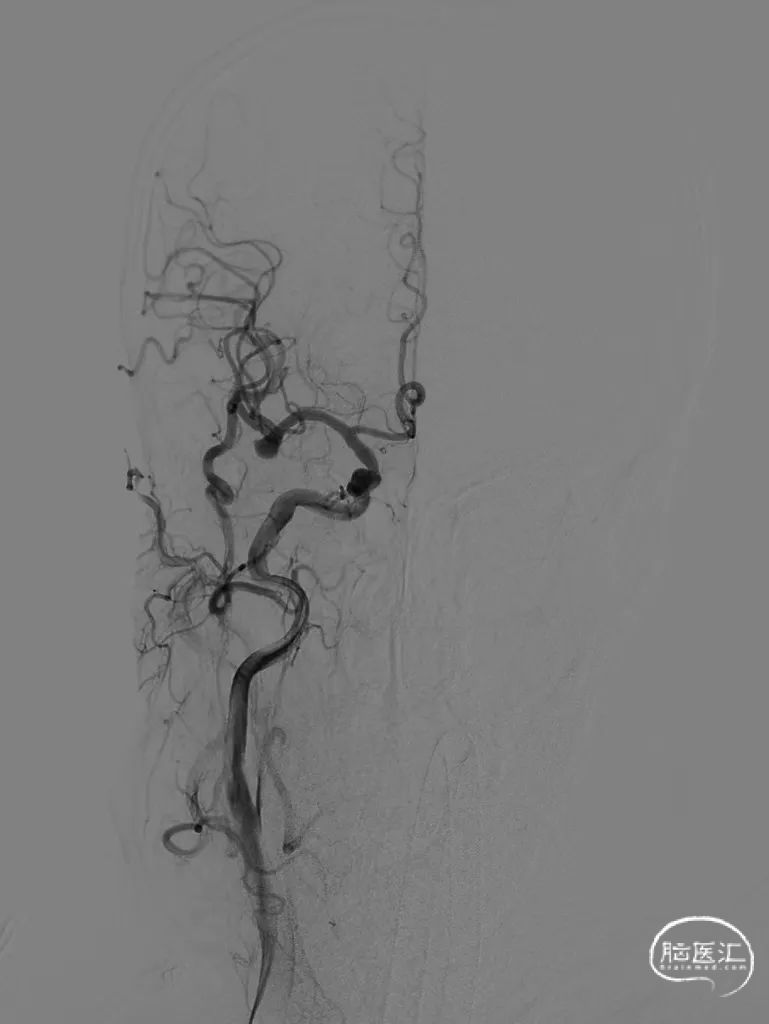

术后影像

术后即刻工作位造影及蒙片:

术后即刻正位造影及蒙片:造影显示瘤体致密栓塞,支架贴壁和导流良好。